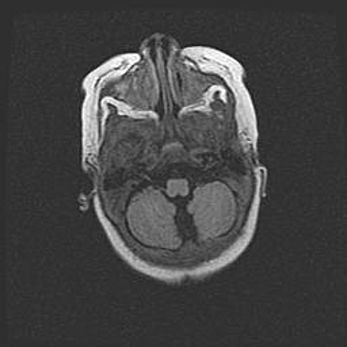

Церебральная ишемия II.

Возраст: 5 дней

Вес: 3400 г

Пол: женский

Окружность головы: 35 см

Срок гестации: 39 недель

Церебральная ишемия – это заболевание, характеризующееся недостаточностью (гипоксией) либо полным прекращением (аноксией) снабжения мозга кислородом по причине закупорки одного или нескольких сосудов. Это приводит к  что метаболическим расстройствам различной степени тяжести в тканях головного мозга, развитию коагуляционных некрозов и гибели нейронов.